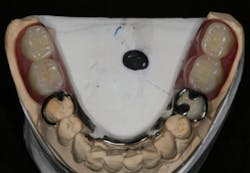

In this case, the diagnostic wax-up of the mounted models gave the technician the new position of the upper incisal edge. The technician then set the maxillary teeth appropriately using models and additional photographs. At the same time, tooth No. 20 was restored, but the lab technician kept the crown and lower partial to predictably create the lower occlusal plane and easily articulate this with the upper immediate denture (figure 18). Note the improved curve of Spee in Figures 19 and 20. Upon completion of the prosthesis, treatment was completed as outlined and the results made the patient feel very comfortable functionally, esthetically, and phonetically.

There was some fine-tuning to the patient's occlusion during the healing period. Nevertheless, the goals of treatment were accomplished very predictably. Figures 21 (horizontal position) and 22 (vertical position) verify both the new vertical and horizontal positions of the upper incisal edge.